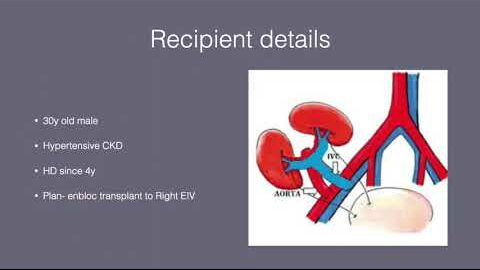

#187 Robotic Assisted Enbloc Dual Kidney Transplant Dr. Sreeharsha Harinatha

KS Awards, Robotics, Surgeon ';